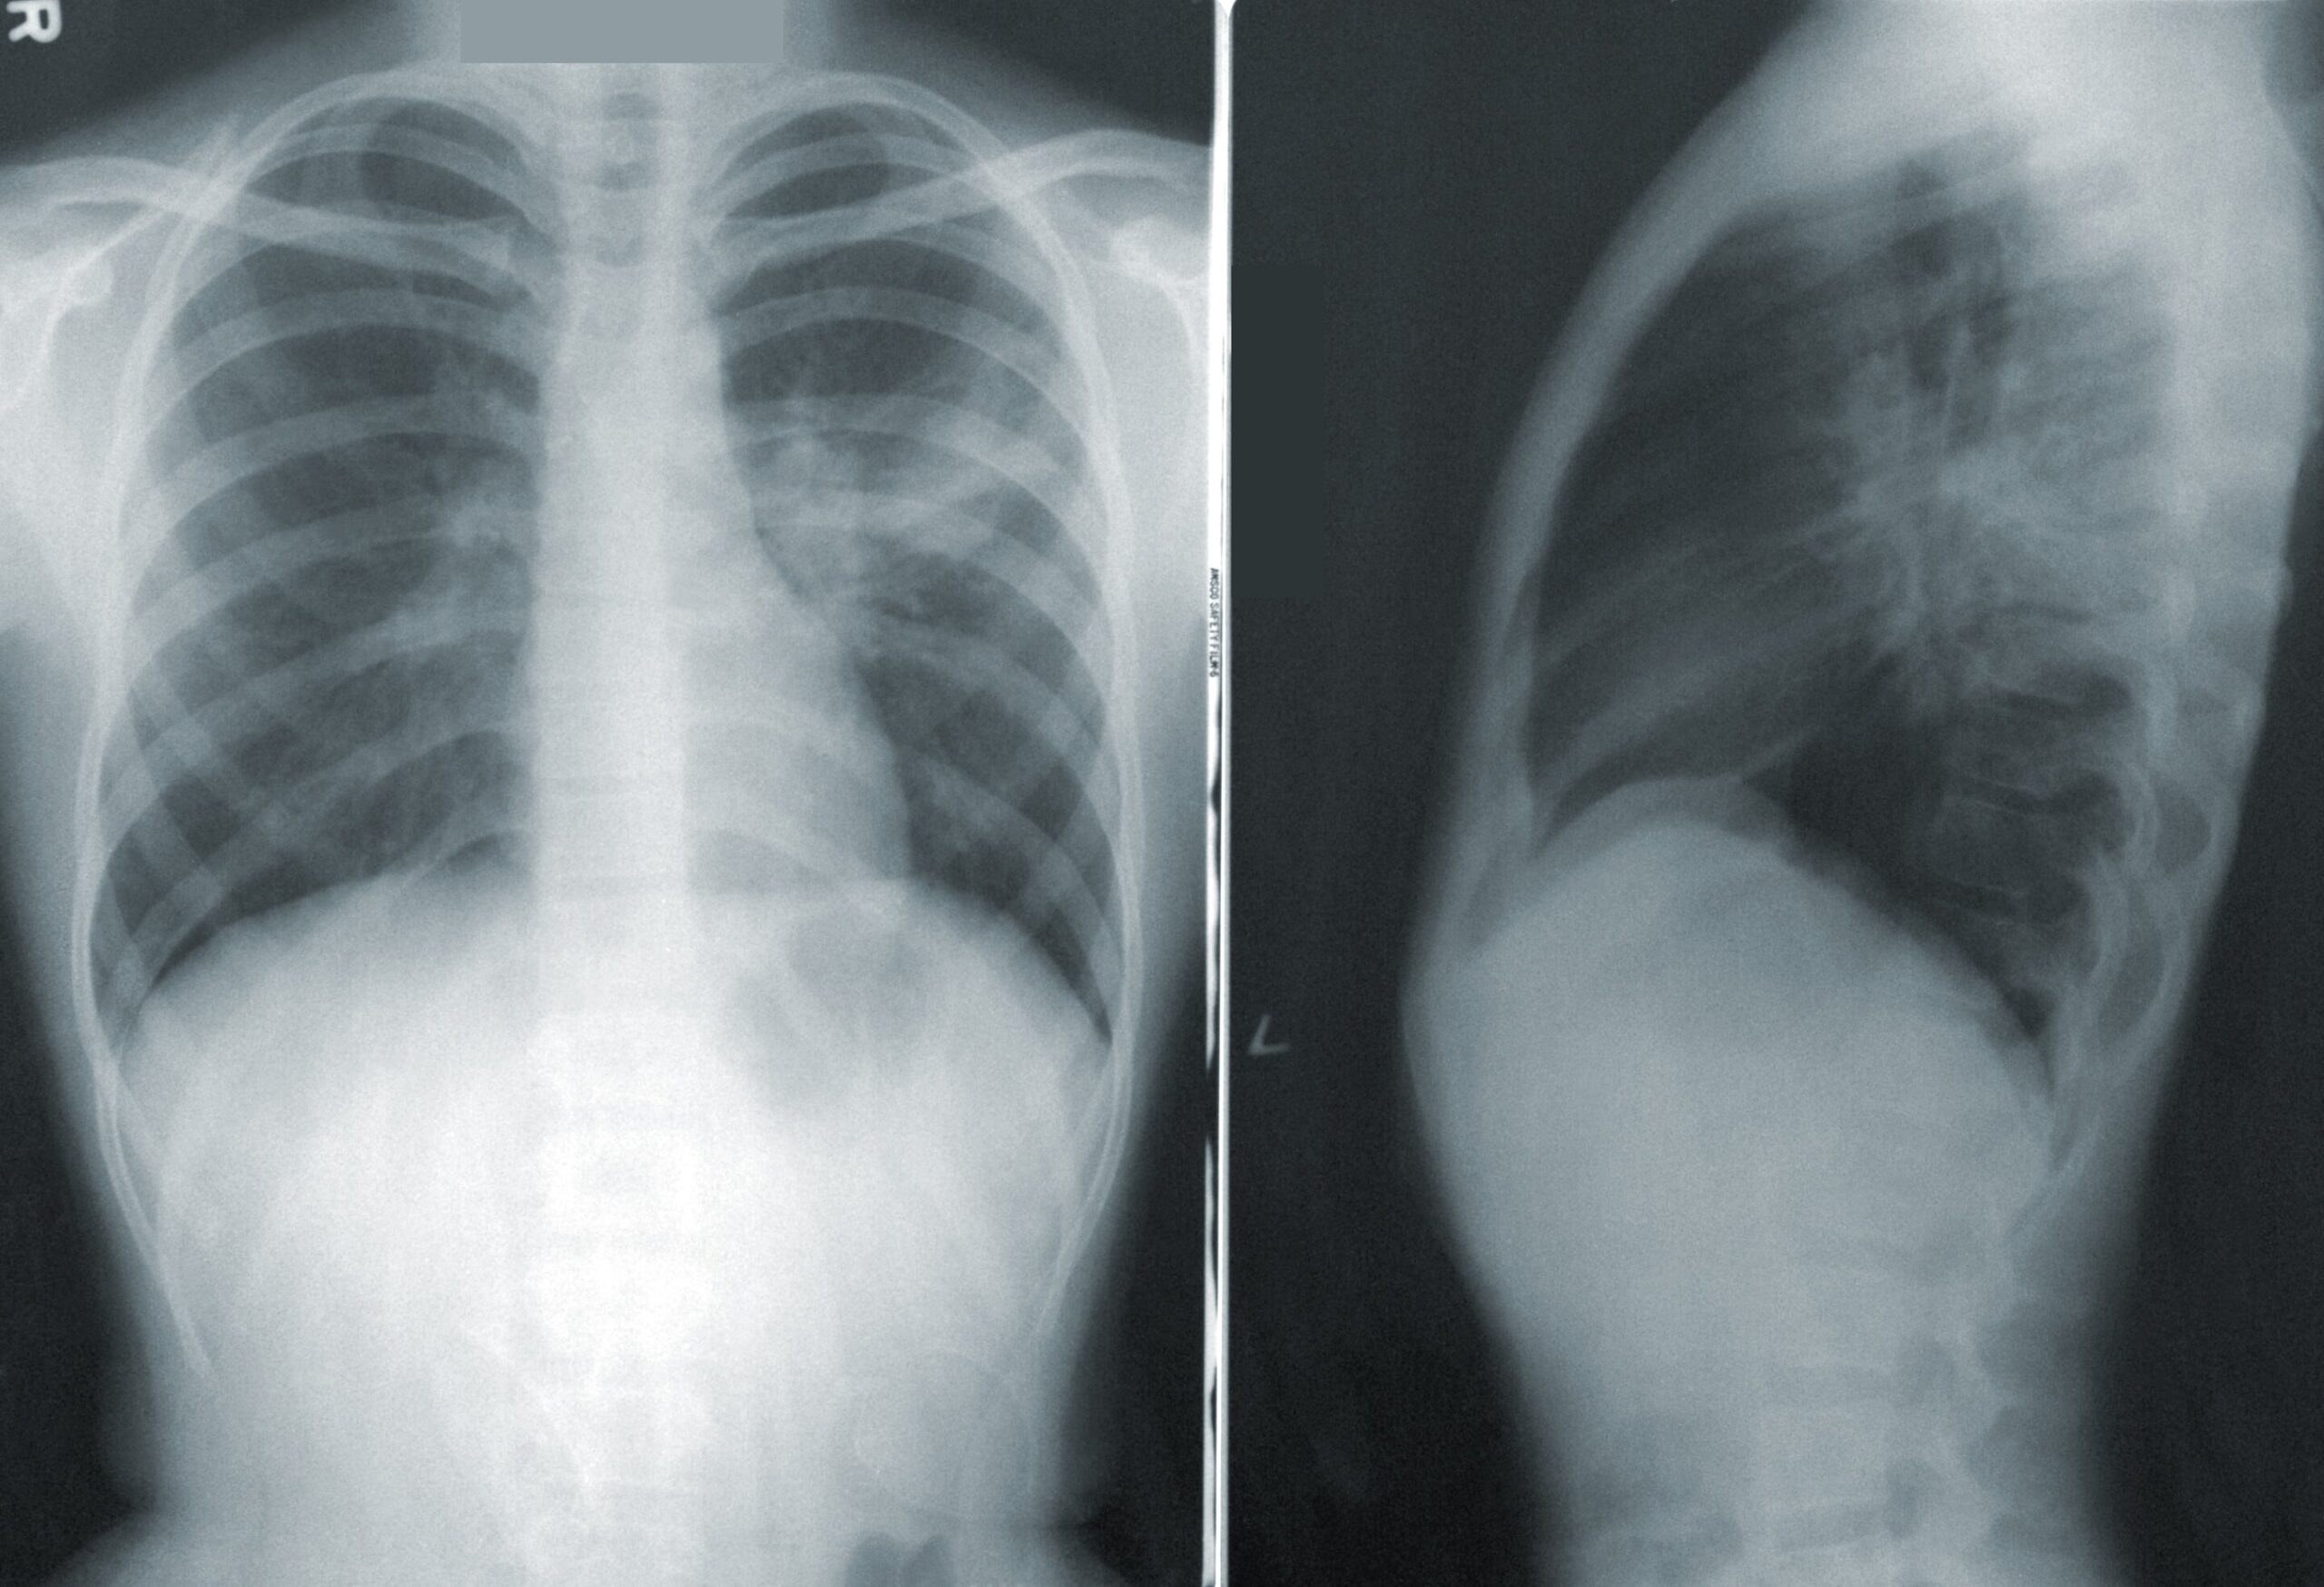

Actuellement, les lignes directrices recommandent un examen tomodensitométrique annuel à faible dose pour les personnes âgées de 50 à 80 ans qui fument actuellement ou qui ont arrêté dans les 15 ans et qui ont fumé une durée de vie équivalente à 20 paquets-années (c’est-à-dire un paquet de cigarettes par jour pendant 20 ans ou deux paquets par jour pendant 10 ans, etc.).